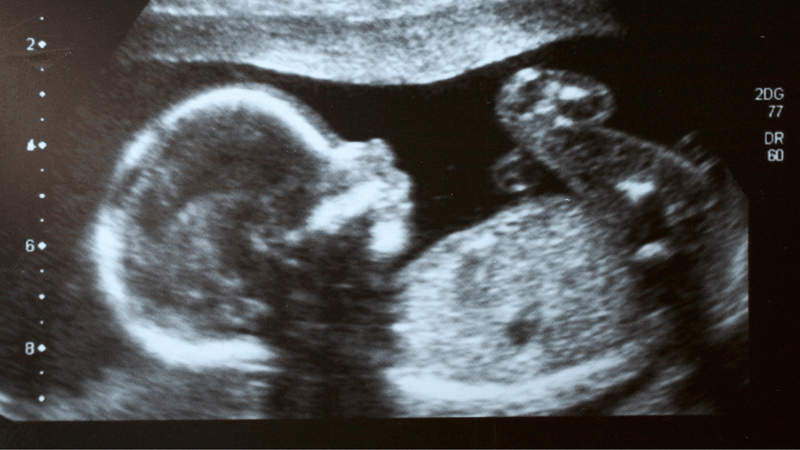

Kể từ khi kỹ thuật thụ tinh trong ống nghiệm (IVF) ra đời, chuyển phôi là bước giúp đưa phôi vào buồng tử cung để tiếp tục phát triển trong cơ thể người mẹ. Hiện nay, có hai phương pháp được áp dụng phổ biến: chuyển phôi tươi và chuyển phôi trữ lạnh. Mỗi phương án có đặc điểm và chỉ định khác nhau, vậy chuyển phôi tươi hay chuyển phôi trữ sẽ phù hợp hơn trong quá trình IVF?